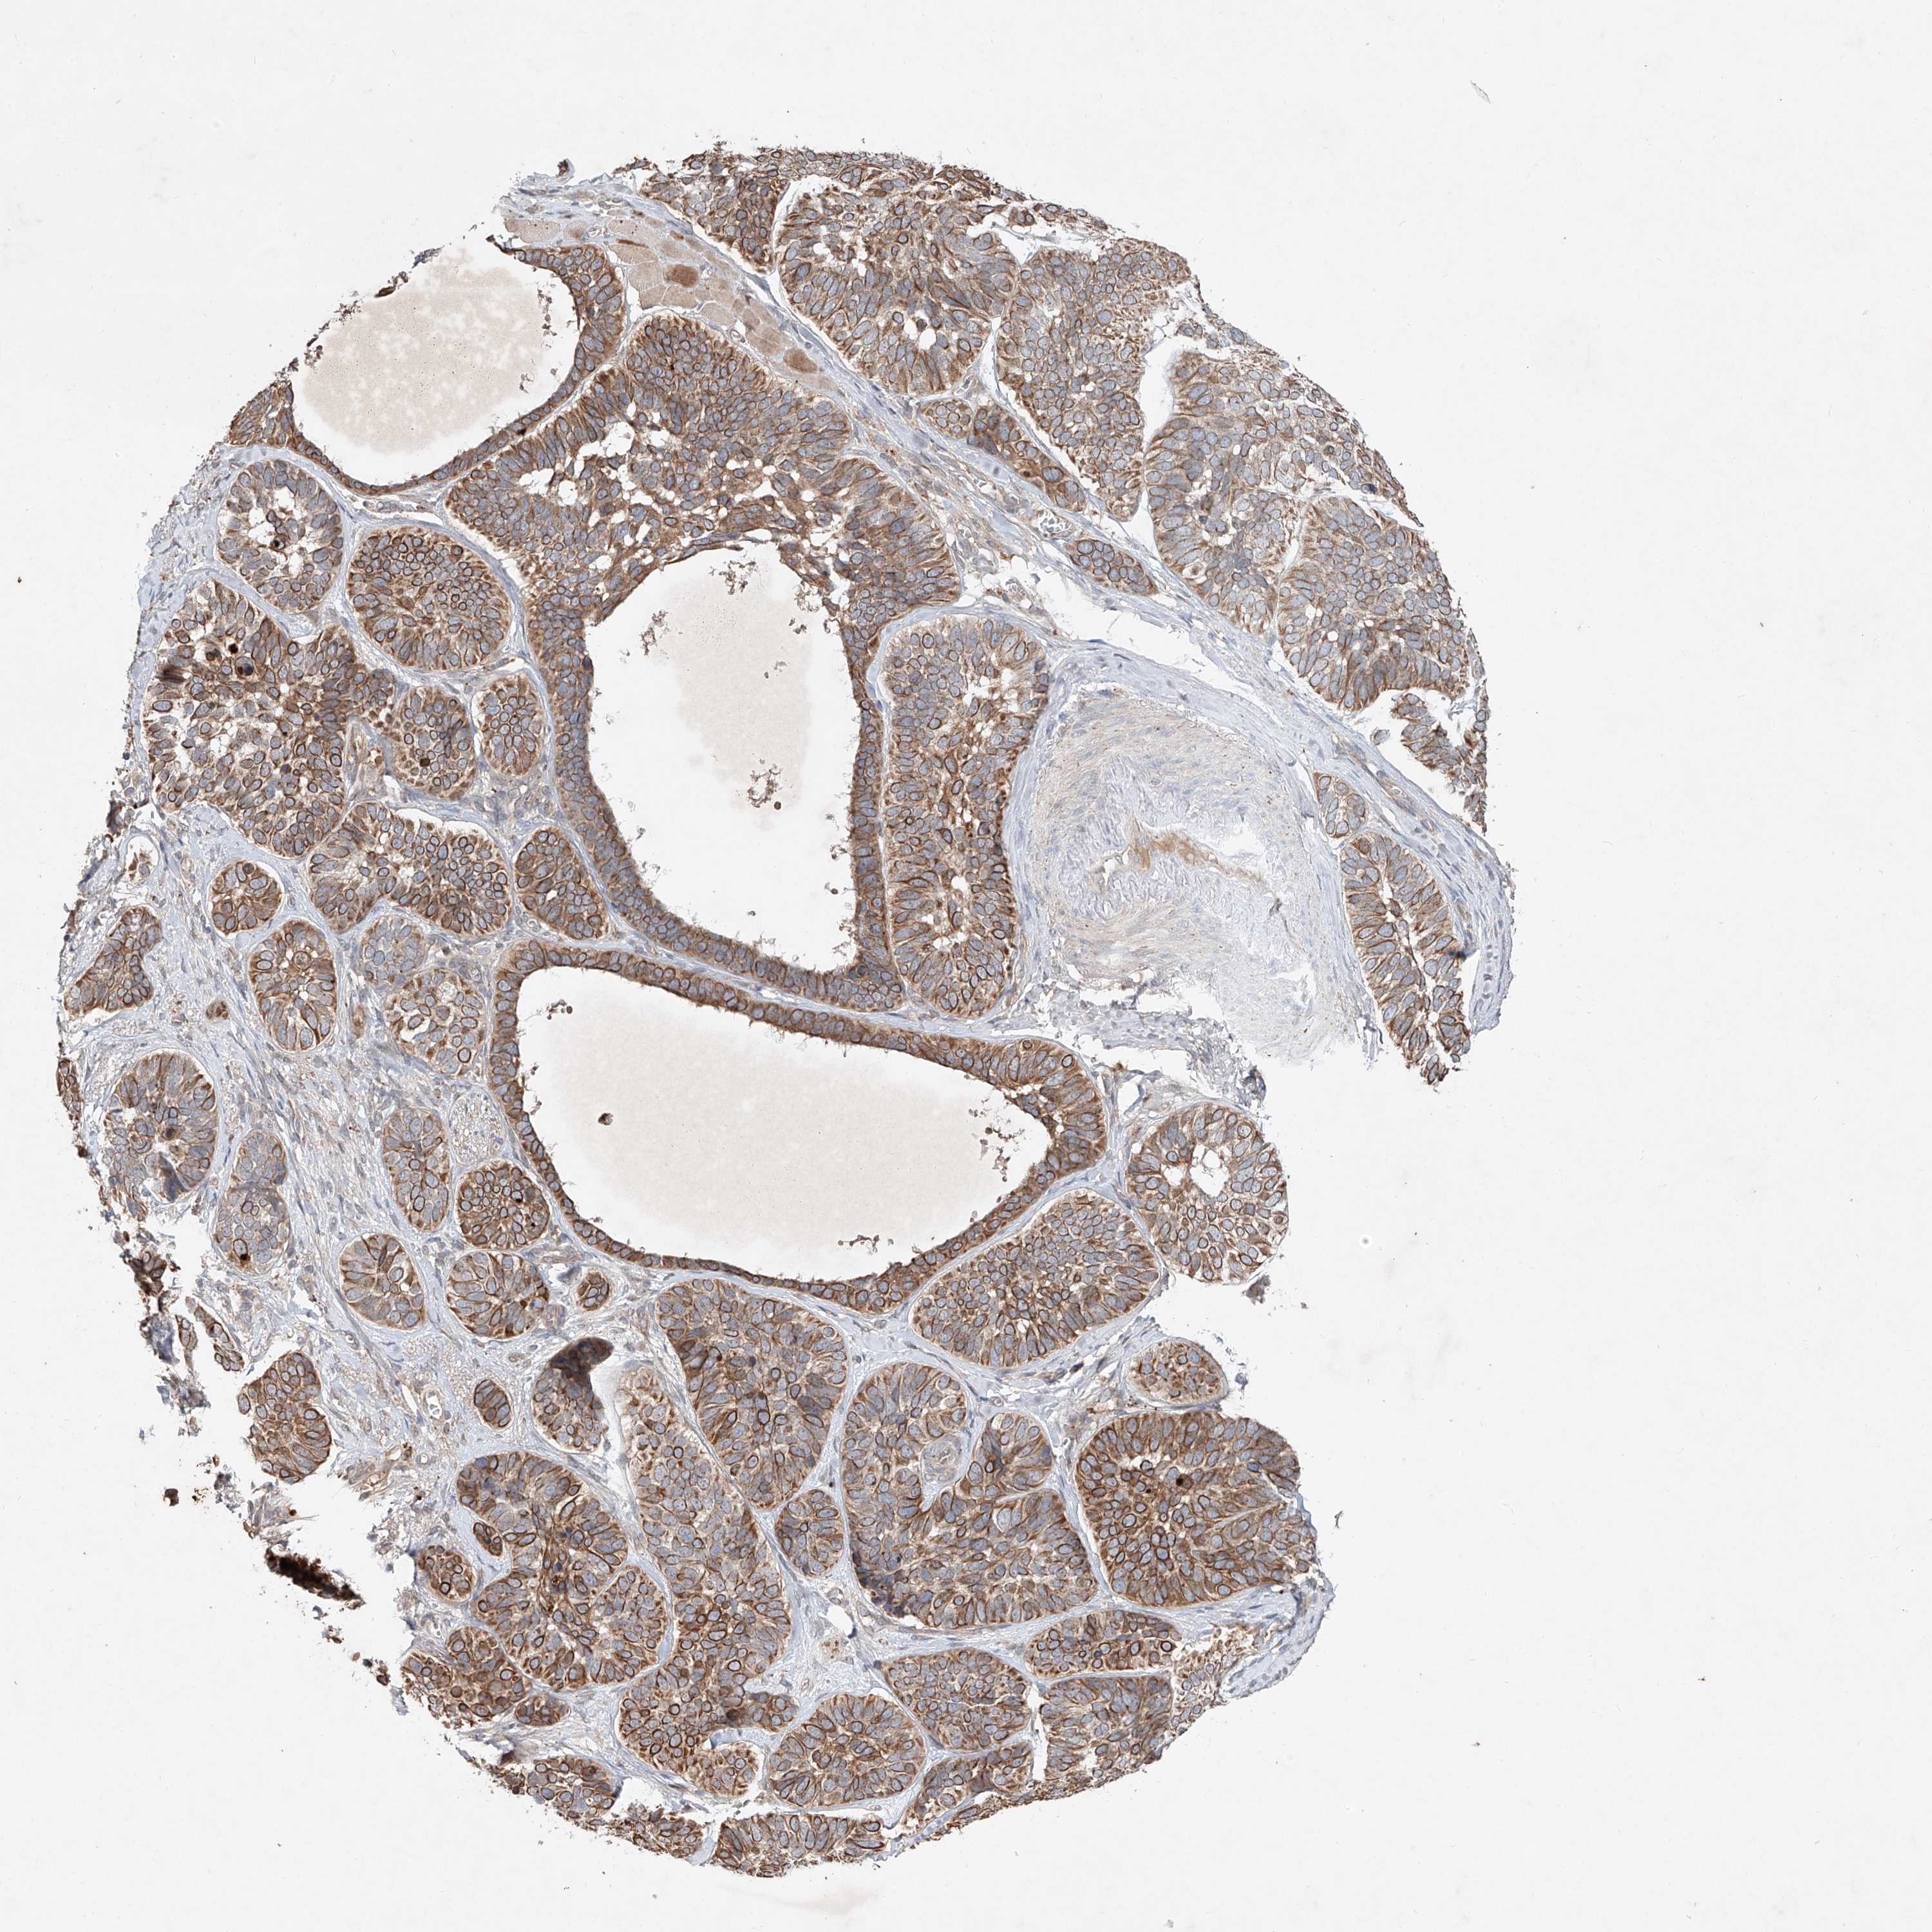

SKIN CANCER - Protein expressioni

A mouse-over function shows sample information and annotation data. Click on an image to view it in a full screen mode. Samples can be filtered based on level of antibody staining by selecting one or several of the following categories: high, medium, low and not detected. The assay and annotation is described here.

Antibody staining in the annotated cell types in the current human tissue is reported as not detected, low, medium, or high, based on conventional immunohistochemistry profiling in selected tissues. This score is based on the combination of the staining intensity and fraction of stained cells.

Each image is clickable and will lead to virtual microscopy that enables deeper exploration of all samples and also displays staining intensity scores, fraction scores and subcellular localization as well as patient and tissue information for each sample.

Antibody HPA029894

Staining

High

Intensity

Strong

Quantity

>75%

Location

Nuclear

Basal cell carcinoma

Squamous cell carcinoma, NOS